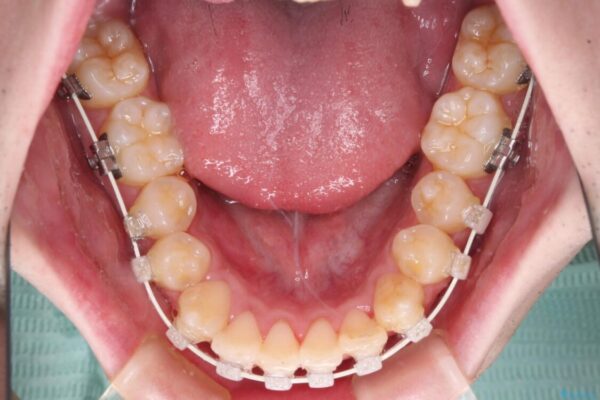

治療途中

• 全顎的なクロスバイト 補助装置を用いてワイヤー矯正 治療途中画像